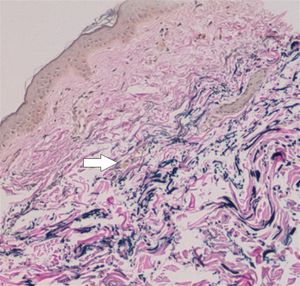

- 병변 피부의 진단적 조직병리학적 변화: 중간 및 하부 진피의 석회화된 탄성 섬유로, 칼슘 염색 양성으로 확인.